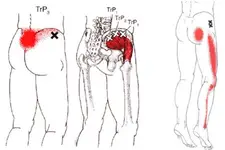

Bel fıtığı, omurlar arasındaki disklerin dış tabakasının yırtılması ve iç kısmının dışarı çıkması sonucu oluşan bir durumu tanımlar. Bu rahatsızlık, sıklıkla şiddetli ağrı, uyuşma, zayıflık ve hareket kısıtlılığı gibi semptomlara yol açar. Bel fıtığına sahip bireylerin fiziksel aktivite yapma yetenekleri sınırlı olabilir, ancak uygun spor ve egzersiz programları, bu kişilerin sağlığını iyileştirebilir. Bu makalede, bel fıtığı olan bireyler için spor yapmanın faydaları detaylandırılacaktır. 1. Ağrı Yönetimi Bel fıtığı, genellikle ağrıya neden olur. Ancak düzenli spor ve egzersiz yapmak, ağrıyı hafifletebilir. Egzersiz, vücudun doğal ağrı kesici mekanizmalarını tetikler ve endorfin salgılar. Ayrıca, kasları güçlendirerek bel bölgesindeki yükü azaltır.

5. Spor Türleri ve Öneriler Bel fıtığı olan bireyler için önerilen spor türleri, düşük etkili egzersizlerdir. Bu tür egzersizler, omurgaya fazla yük bindirmeden güçlenmeye yardımcı olabilir.